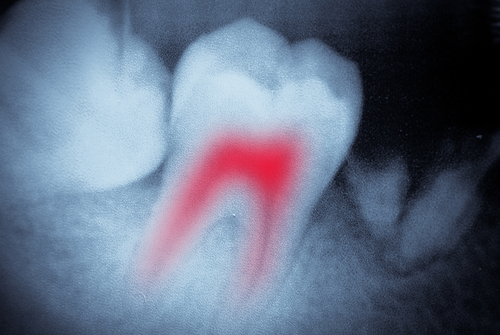

root canal

Tooth Pain? You May Need a Root Canal.

Root canals have a pretty bad reputation as being painful. But the truth is, root canals actually stop the tooth pain. When your tooth becomes so infected or decayed that it hits the inside pulp, it can be incredibly painful. Once your dentist cleans out the area where the roots are located (the canal), and covers it with a filling or dental crown, relief will feel so good.

Before beginning, you’ll be numbed to avoid any discomfort. Once the medication kicks in, your dental team will get to work. First, a tiny hole is made in the infected tooth which allows access to the middle of the tooth, known as the pulp chamber. This is where the root canals are located. The root canals house pulp, nerves, and blood vessels. Your dentist will remove any and all of these materials, making your tooth no longer able to feel anything. After a thorough cleaning, the canals are sealed and the tooth is capped with a restoration.